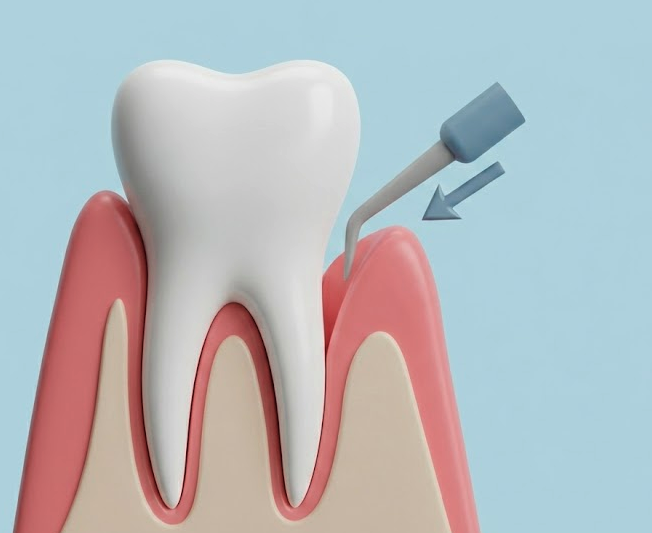

Advanced gum disease sometimes requires surgical treatment. Flap surgery involves lifting the gums to remove tartar deposits deep below the gum line, then repositioning the gums to fit snugly around teeth.

Gum grafting treats recession where gum tissue has pulled away from teeth, exposing roots. This can cause sensitivity and increase decay risk. During grafting, we take tissue from another area of your mouth or use donor tissue to cover exposed roots.